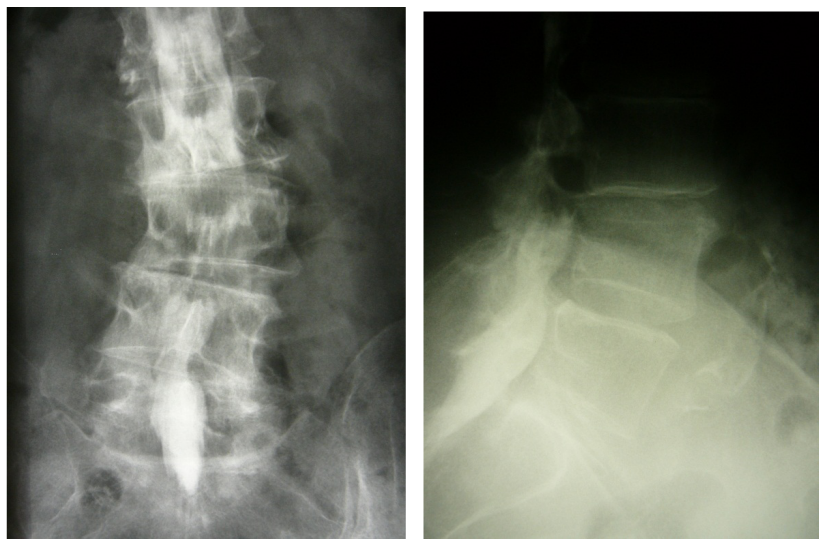

The surgery and follow-up was performed by the author (S.E.). Preoperative diagnoses were degenerative spinal stenosis with instability (Figure 1 [Fig. 1]).

Fusion was assessed at final follow-up on plain anteroposterior and lateral radiographs using the criteria suggested by Christensen et al. [5].